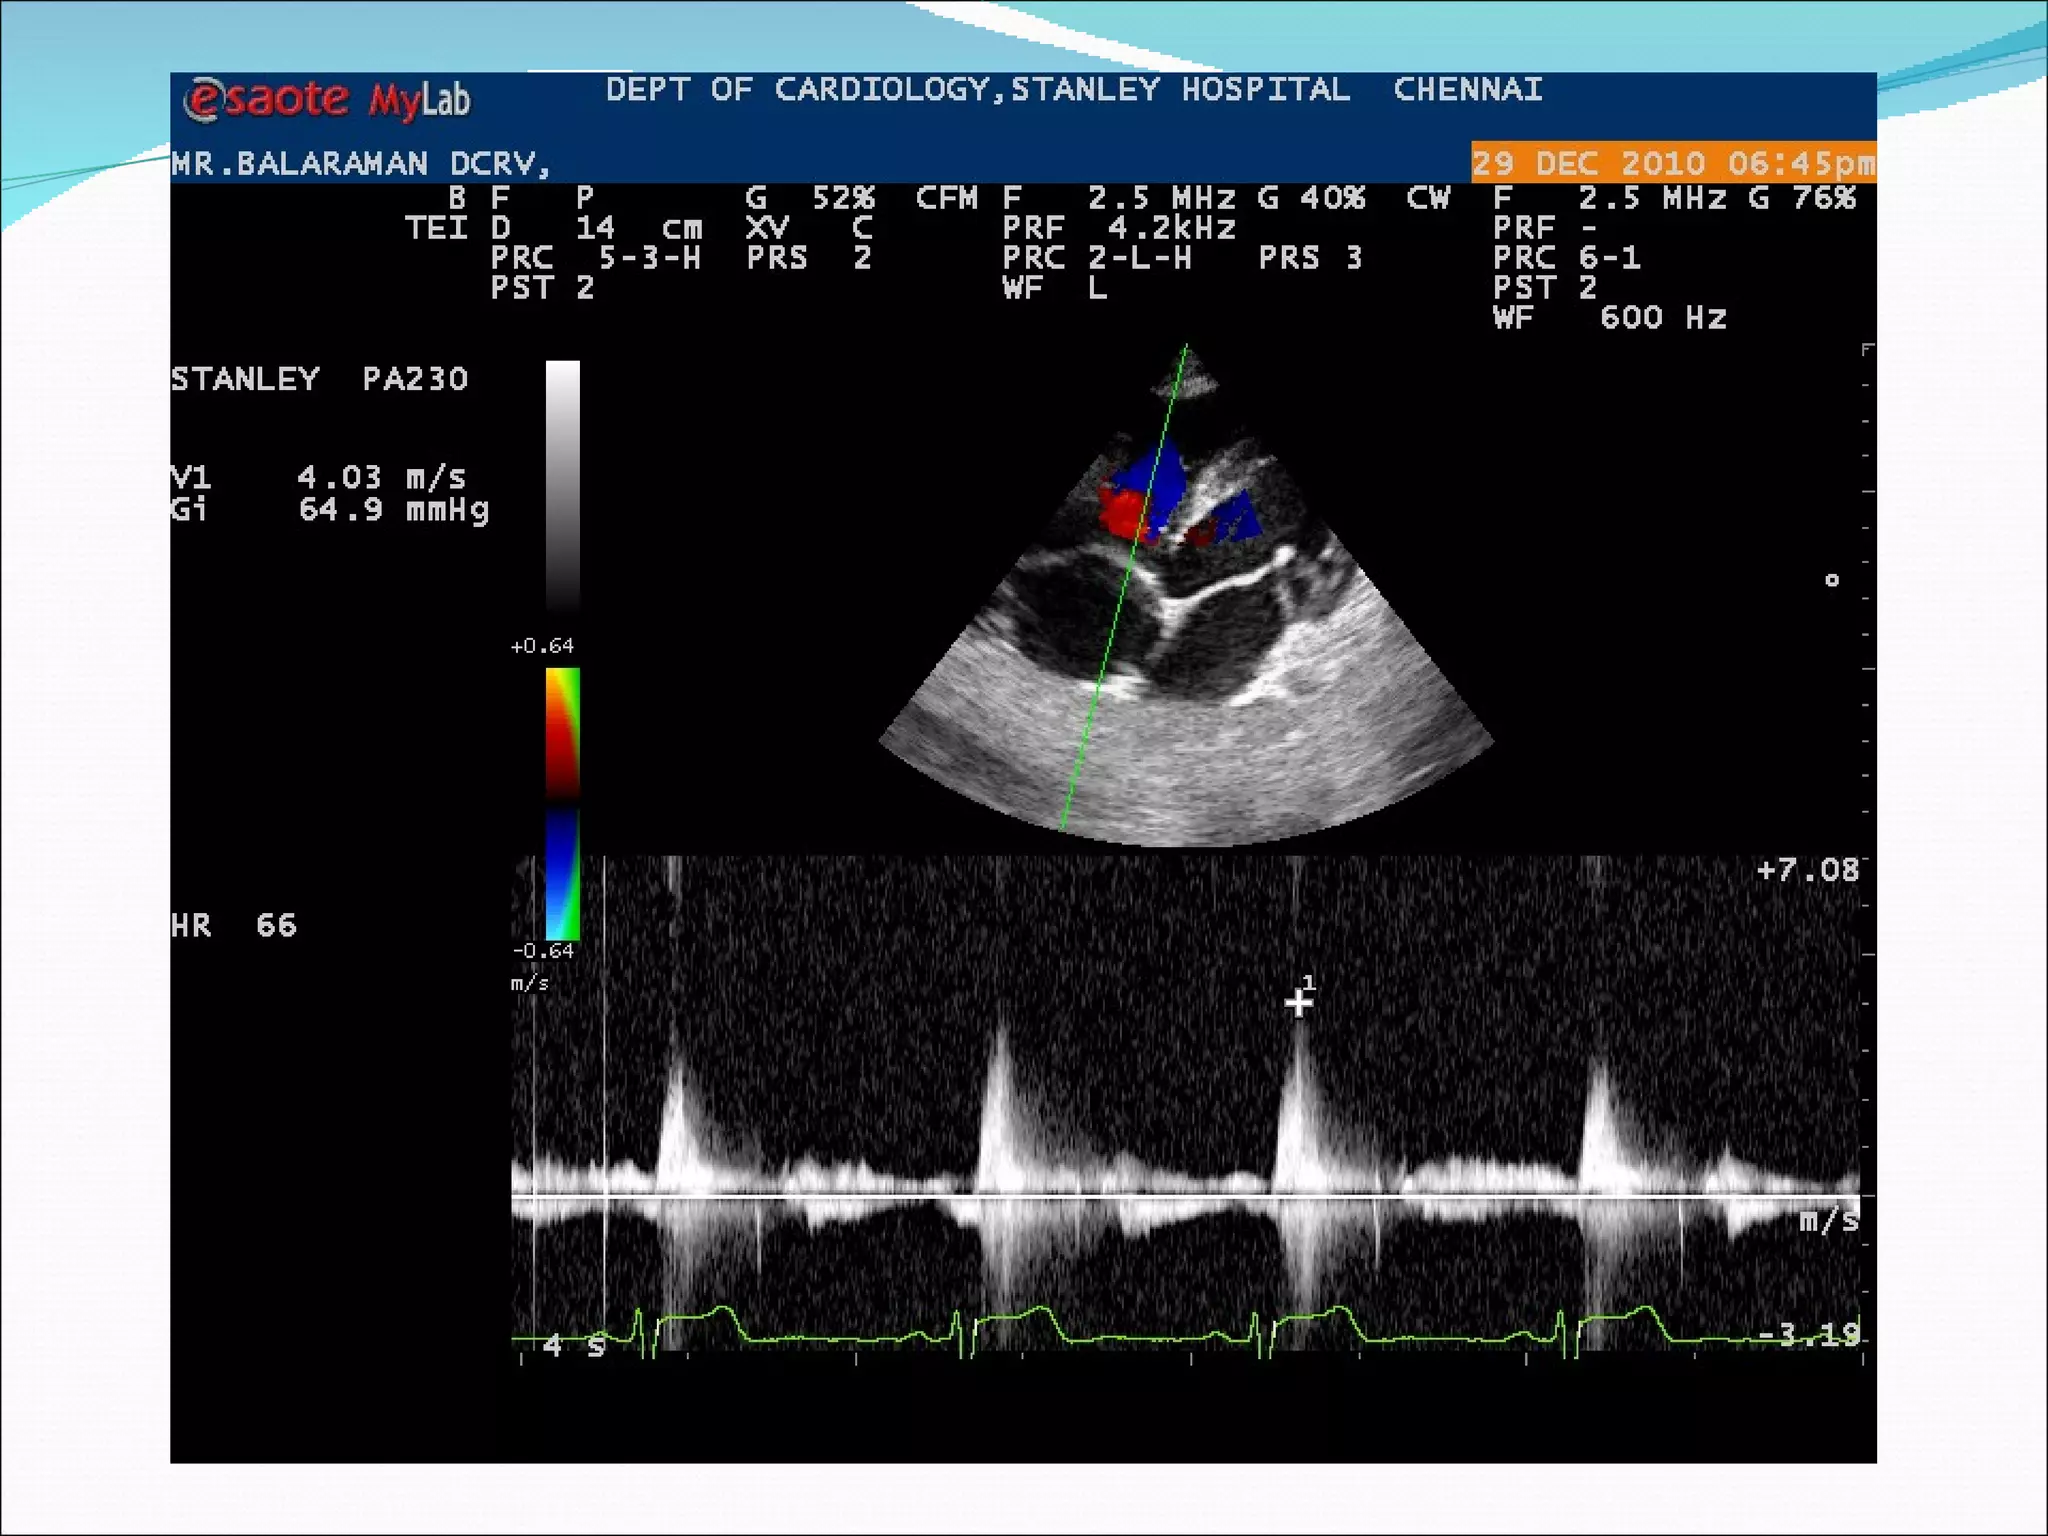

A 20-year-old male patient presented with complaints of palpitations and exertional breathlessness. On examination, he had a heart rate of 64 beats per minute, blood pressure of 100/70 mmHg, and a grade 5/6 pansystolic murmur heard best over the left parasternal area. An ECG showed right ventricular hypertrophy and right axis deviation. An echocardiogram confirmed the diagnoses of a ventricular septal defect and double chambered right ventricle.